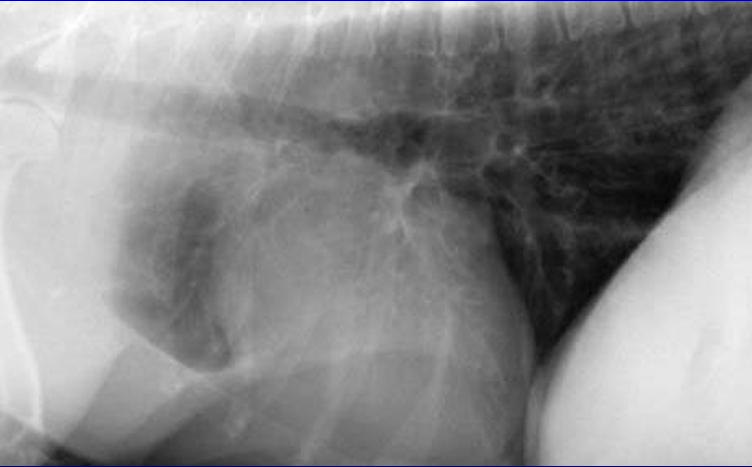

| ๊ฒฝ๋ถ ๋ฐฉ์ฌ์ | |

|---|---|

![]() | - ๊ฒฝ๋ถ ์ชฝ lateral ์ดฌ์์์ trachea์ dorsal ์ชฝ์ผ๋ก ๊ฒน์น ์์์ด ๋ณด์. - Trachea์ dorsal band๊ฐ ์ถ ์ณ์ ธ์ ์ด๋ ๊ฒ ๋ณด์ผ ์๋ ์์ง๋ง (์ด ๊ฒฝ์ฐ๋ tracheoscopy๋ก ๊ฐ๋ณ + dorsal membrane์ด ์ถ ๋์ด์ง๋ฉด trachea๊ฐ ๋ฌด๋์ง๋ ๊ฒฝํฅ), - ์ฐ๊ณจ ์์์ด ์ด์ง ๋ณด์ด๋ฉด์ diameter๊ฐ ์ผ์ ํ ๊ฒ์ ๋ณด๋ฉด ์๋์ ๊ฒน์น ๊ฒ์ผ๋ก ๋ณด๋ ๊ฒ์ด ํ๋น. |